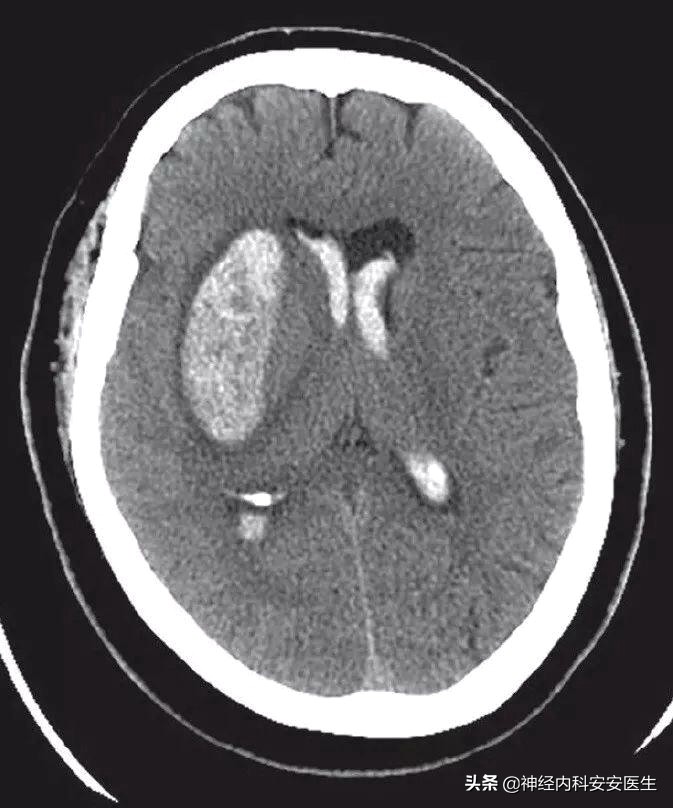

此为脑出血的CT片子,脑实质中白色区域为脑出血的地方